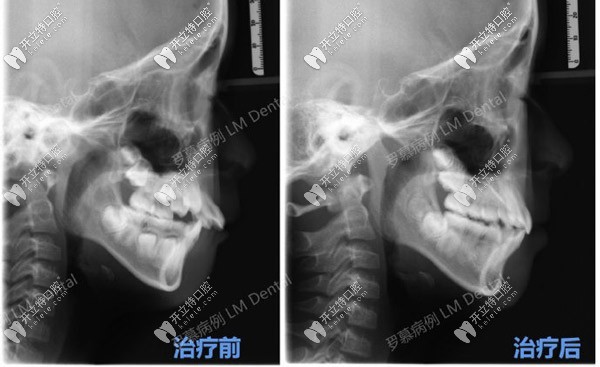

主要使用的是羅慕咬合誘導(dǎo)矯正,針對(duì)于深覆合/蓋、開(kāi)頜、牙列擁擠、前牙間隙以及反頜都有不錯(cuò)的效果。